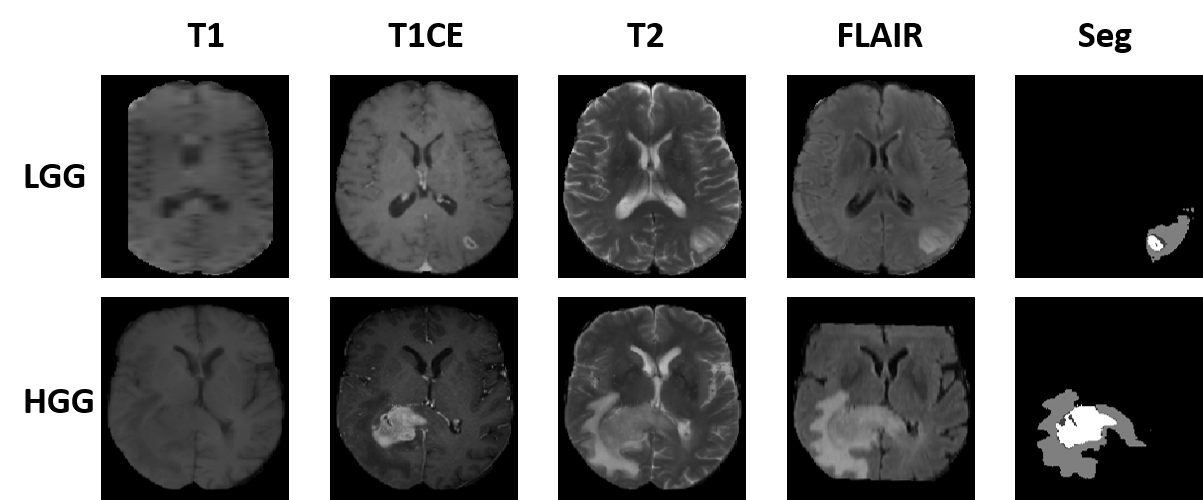

Fig. 5: Illustration of the tumor size variability in the BraTS2018 database: the top row shows axial slices of LGG (top row) and HGG (bottom row) tumors with four MRI modalities and the corresponding segmentation label used in this work.

Each patient has 4 registered Magnetic Resonance (MR) Imaging (MRI) modalities, i.e., T1-weighted (T1), T1-contrast enhanced (T1ce), T2-weighted (T2), and T2 Fluid Attenuated Inversion Recovery (FLAIR) MRI. The MRI voxels have four class labels, i.e., enhancing tumor (EnhT), peritumoral edema (ED), tumor core (CoreT), and background. The union of CoreT, ED, and EnhT represents the whole tumor [52]. To demonstrate the validity and generality of the proposed OSUDA, we carried out two cross-domain protocols, including cross-modality [70] and cross-subtype UDA [52]. Fig. 5 shows example samples with the four MRI modalities from HGG or LGG datasets. Because there are imaging artifacts/low resolution in some slices (e.g., LGG T1 slice) and partly because of the cross-modality registration as a preprocessing [46], some of the structures are incomplete. We note that the image volumes in BraTS have different resolution, and have been co-registered, interpolated to a standard resolution [46].